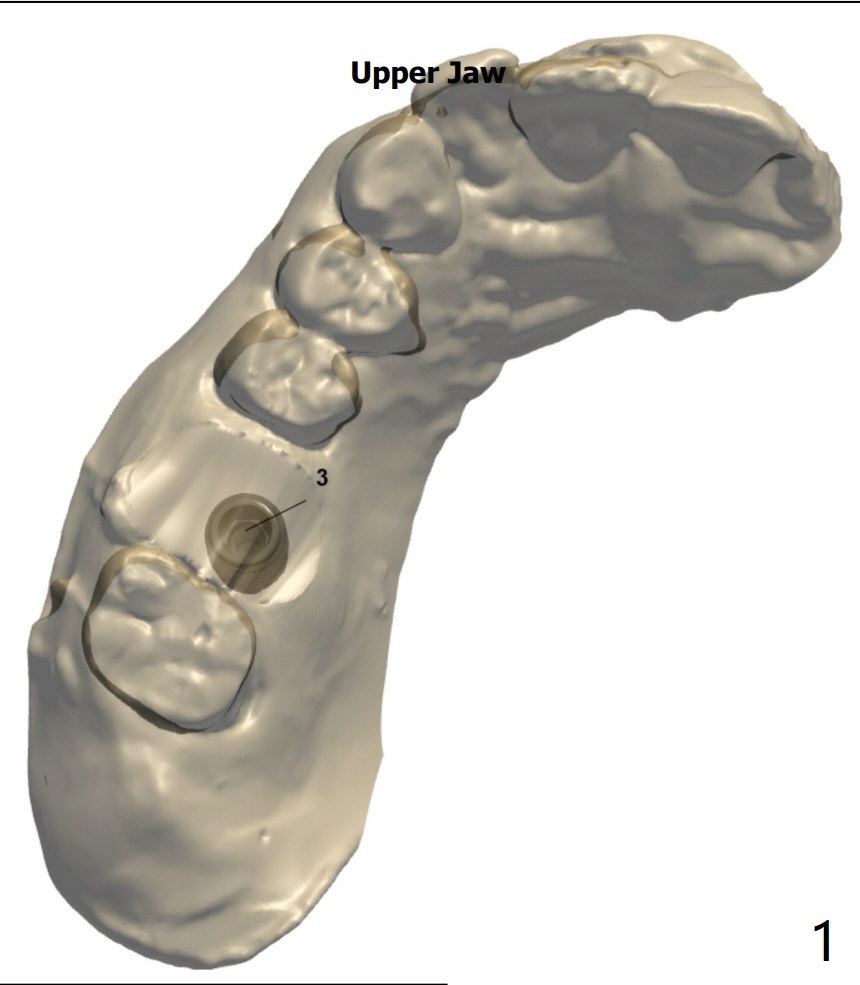

Return to No Caries  手术

Xin Wei, DDS, PhD, MS 1st edition 12/04/2020, last revision 12/17/2020